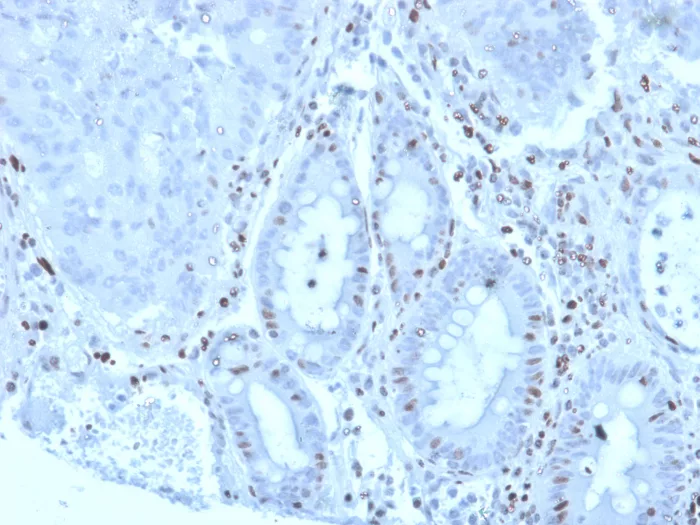

Formalin-fixed, paraffin-embedded human colon carcinoma stained with MZF1 Mouse Monoclonal Antibody (PCRP-MZF1-1E8). HIER: Tris/EDTA, pH9.0, 45min. 2°C: HRP-polymer, 30min. DAB, 5min.